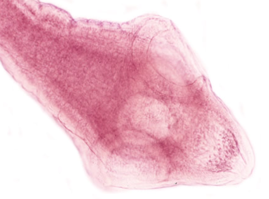

Taenia saginata, carmine, >12

Mature proglottid of ____________, stained with ____________. Note the number of uterine branches.